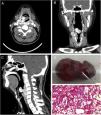

A 39-year-old man was admitted to our department with a 2-months history of foreign body sensation in the throat and aggravated 1 week. He complained of intermittent cough. No dyspnoea and dysphagia. Contrast-enhanced computed tomography revealed a strikingly enhancing tumor located the pharyngoesophageal junction with a mass protruding into the laryngeal vestibule. Images from transverse (Panel A), coronal (Panel B) and sagittal (Panel C) planes showed a bilateral hypopharynx and pharyngoesophageal junction enhancing mass. The tumor was extending outward through the cricothyroid space and indistinguishable from the right upper pole of the thyroid. A surgical resection of the tumor was planed. However, he suddenly coughed up a tumor mass with a small amount of bleeding and blood clot on the second night after hospitalization. The size of the coughed up tumor mass is 2cm×3cm×1cm (Panel D). The pathological result suggested that the coughed tumor is hemangiomatous polyp (Panel E). Considering the risk of massive bleeding, transarterial embolization was performed for the remaining polypoid lesion and the tumor located at the hypopharynx and pharyngoesophageal junction. The final pathological result of the surgical sample indicated that the tumor was renal clear cell carcinoma metastasis. The left renal mass was confirmed on US and CT after the diagnosis. Subramanyam et al.1 reported one similar case (Fig. 1).